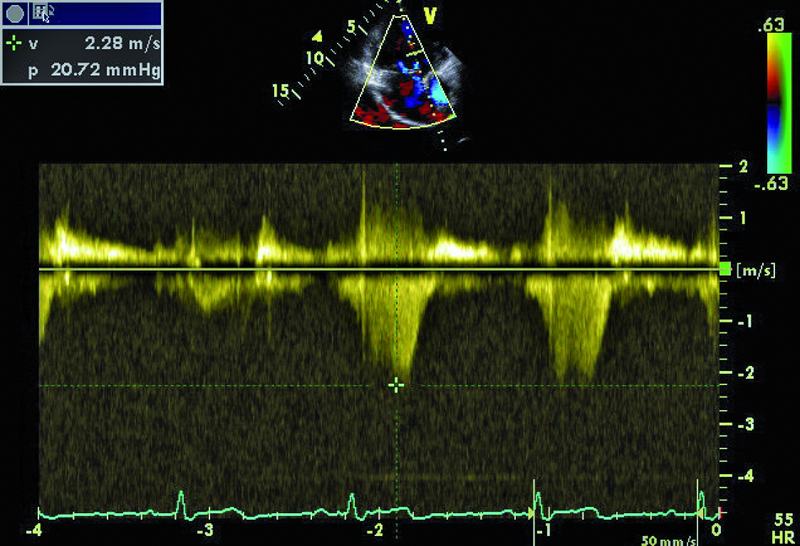

Cechy anomalii Ebsteina łatwo zidentyfikować. Należy zwrócić uwagę na odległość między przyczepem płatka przegrodowego zastawki trójdzielnej a przyczepem przedniego płatka zastawki mitralnej (ryc. 1). Fizjologiczne przesunięcie płatków jest niewielkie i zwykle nie przekracza 5-10 mm. Za kryterium rozpoznania anomalii uważa się wartość 20 mm (w przedstawionym przypadku 50 mm). Przemieszczone płatki są zwykle zmienione organicznie, pogrubiałe, często pociągane przez struny ścięgniste. Płatek przedni jest prawidłowo przyczepiony do pierścienia zastawki trójdzielnej, natomiast jest zwykle powiększony i kształtem może przypominać żagiel (ryc. 1-3). Cechą płatka przedniego w anomalii Ebsteina jest także jego nadmierna ruchomość i liczne perforacje powodujące zwykle więcej niż jedną falę zwrotną (ryc. 4). Zatrializowana część prawej komory znajduje się między przemieszczonymi przyczepami płatków przegrodowego i tylnego, a właściwa jama ma zmniejszoną pojemność. To, czy wada daje objawy, zależy od nasilenia niedomykalności trójdzielnej i od współistniejących anomalii. Niedomykalność trójdzielna u tego pacjenta, mimo dużego przemieszczenia płatka przegrodowego, była mała (ryc. 4). Zarejestrowany metodą doplerowską profil prędkości z jednego ze strumieni niedomykalności wskazywał na niepodwyższone ciśnienie w jamie prawej komory (ryc. 5). Funkcja mięśnia prawej komory określona za pomocą pomiaru przemieszczenia bocznej części pierścienia zastawki trójdzielnej była prawidłowa (ryc. 6). Diagnostykę można na tym etapie zakończyć i uznać, że chory kwalifikuje się do dalszej obserwacji. Badanie przezprzełykowe jest potrzebne u pacjentów, u których nie można ocenić dokładnie morfologii zastawki trójdzielnej. Może też być konieczne w przypadku desaturacji krwi tętniczej i podejrzenia często towarzyszącego anomalii ubytku przegrody międzyprzedsionkowej. Warto zaznaczyć, że ubytek zwykle charakteryzuje się przeciekiem prawo-lewym, na skutek dysfunkcji jam prawego serca i wzrostu ciśnienia w jamie prawego przedsionka. W tym przypadku, wobec braku sinicy, badania przezprzełykowego nie wykonano. Cewnikowanie serca także nie jest konieczne, ponieważ chory ma małą niedomykalność trójdzielną i dobrą wydolność fizyczną, a więc nie kwalifikuje się do leczenia operacyjnego.